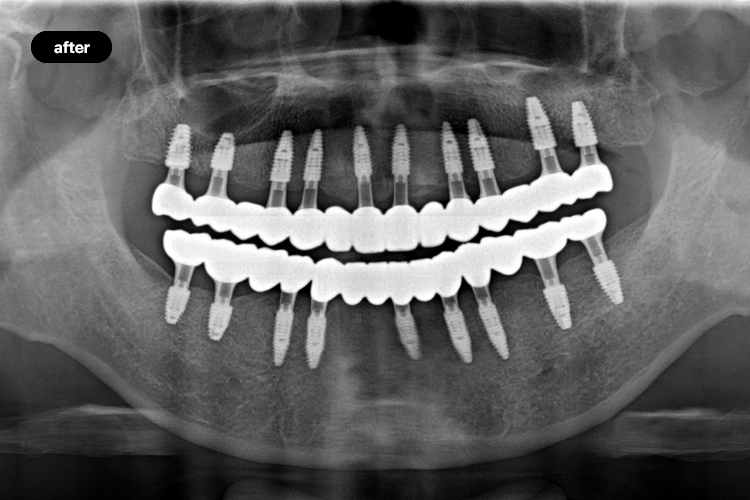

• Full-Mouth Implants

Many clinics perform implant treatment.

However, few excel in complex procedures

such as full-mouth implants.

Because full-mouth implants involve highly advanced surgery, precise diagnosis and systematic processes are critical. At MIR Dental Hospital, digital systems enable accurate and precise treatment. After establishing a detailed surgical plan, we perform minimally invasive incisions and place implants precisely in the planned position, followed by customized prosthetic restoration.

• #Full-Mouth Implant Specialist

• #Perfect Smile

• #Improved Quality of Life

• #Strong Foundation from the Jawbone

• #Choosing the Right Dental Hospital Matters